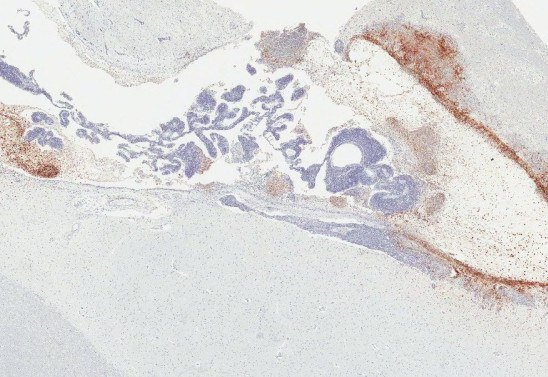

O grupo avaliou mais de 10 macacos infectados pelo ebola e tratados da mesma forma que humanos com a doença. Análises mostraram que o vírus estava escondido em uma região de alto risco. "Descobrimos que cerca de 20% dos macacos que sobreviveram à exposição letal ao ebola após o tratamento com terapia de anticorpos monoclonais tinham resquícios da infecção especificamente no sistema ventricular cerebral, local em que o líquido cefalorraquidiano é produzido, mesmo quando o vírus havia sido eliminado de todos os outros órgãos", detalha Zeng.

Os dados entram em concordância com o caso de uma enfermeira britânica que apresentou meningoencefalite, uma inflamação cerebral, nove meses depois de se recuperar da doença. A paciente também havia recebido anticorpos monoclonais. "Vemos claramente que esse vírus pode se reativar e causar recaídas nos sobreviventes", destacaram os autores.